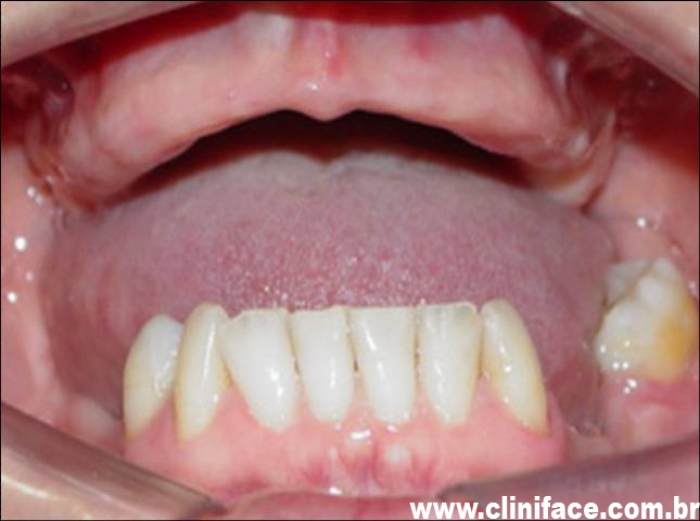

Imagem inicial